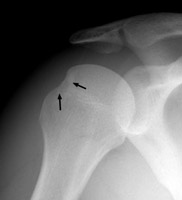

Diagnosis:s/p anterior shoulder dislocation Discussion:Frontal film of the right shoulder which reveals a defect of the posterolateral aspect of the humeral head, consistent with a Hill-Sachs deformity. The Hill-Sachs sign represents deformity of the superior, posterior border of the humeral head and is typically a result of impaction of the anterior inferior surface of the glenoid labrum on the posterolateral aspect of the humeral head during dislocation. References: